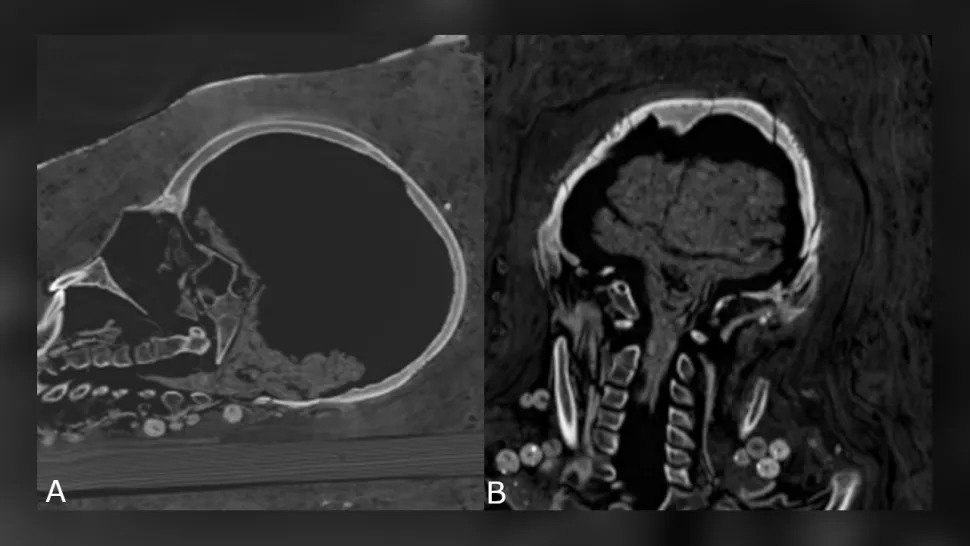

Tudi možgani ženske niso bili ohranjeni, vendar so bili ohranjeni možgani mladostnika – skrčili so se, možgane in možgansko deblo pa je bilo še vedno mogoče prepoznati – in tudi drugi notranji organi mladostnika.

Krčenje najstniških možganov. (Zesh et al., PLOS One, 2020)

“Zelo verjetno je, da so mumije preživele le zaradi neke vrste dehidracije z [dehidracijsko mešanico] natrona.”